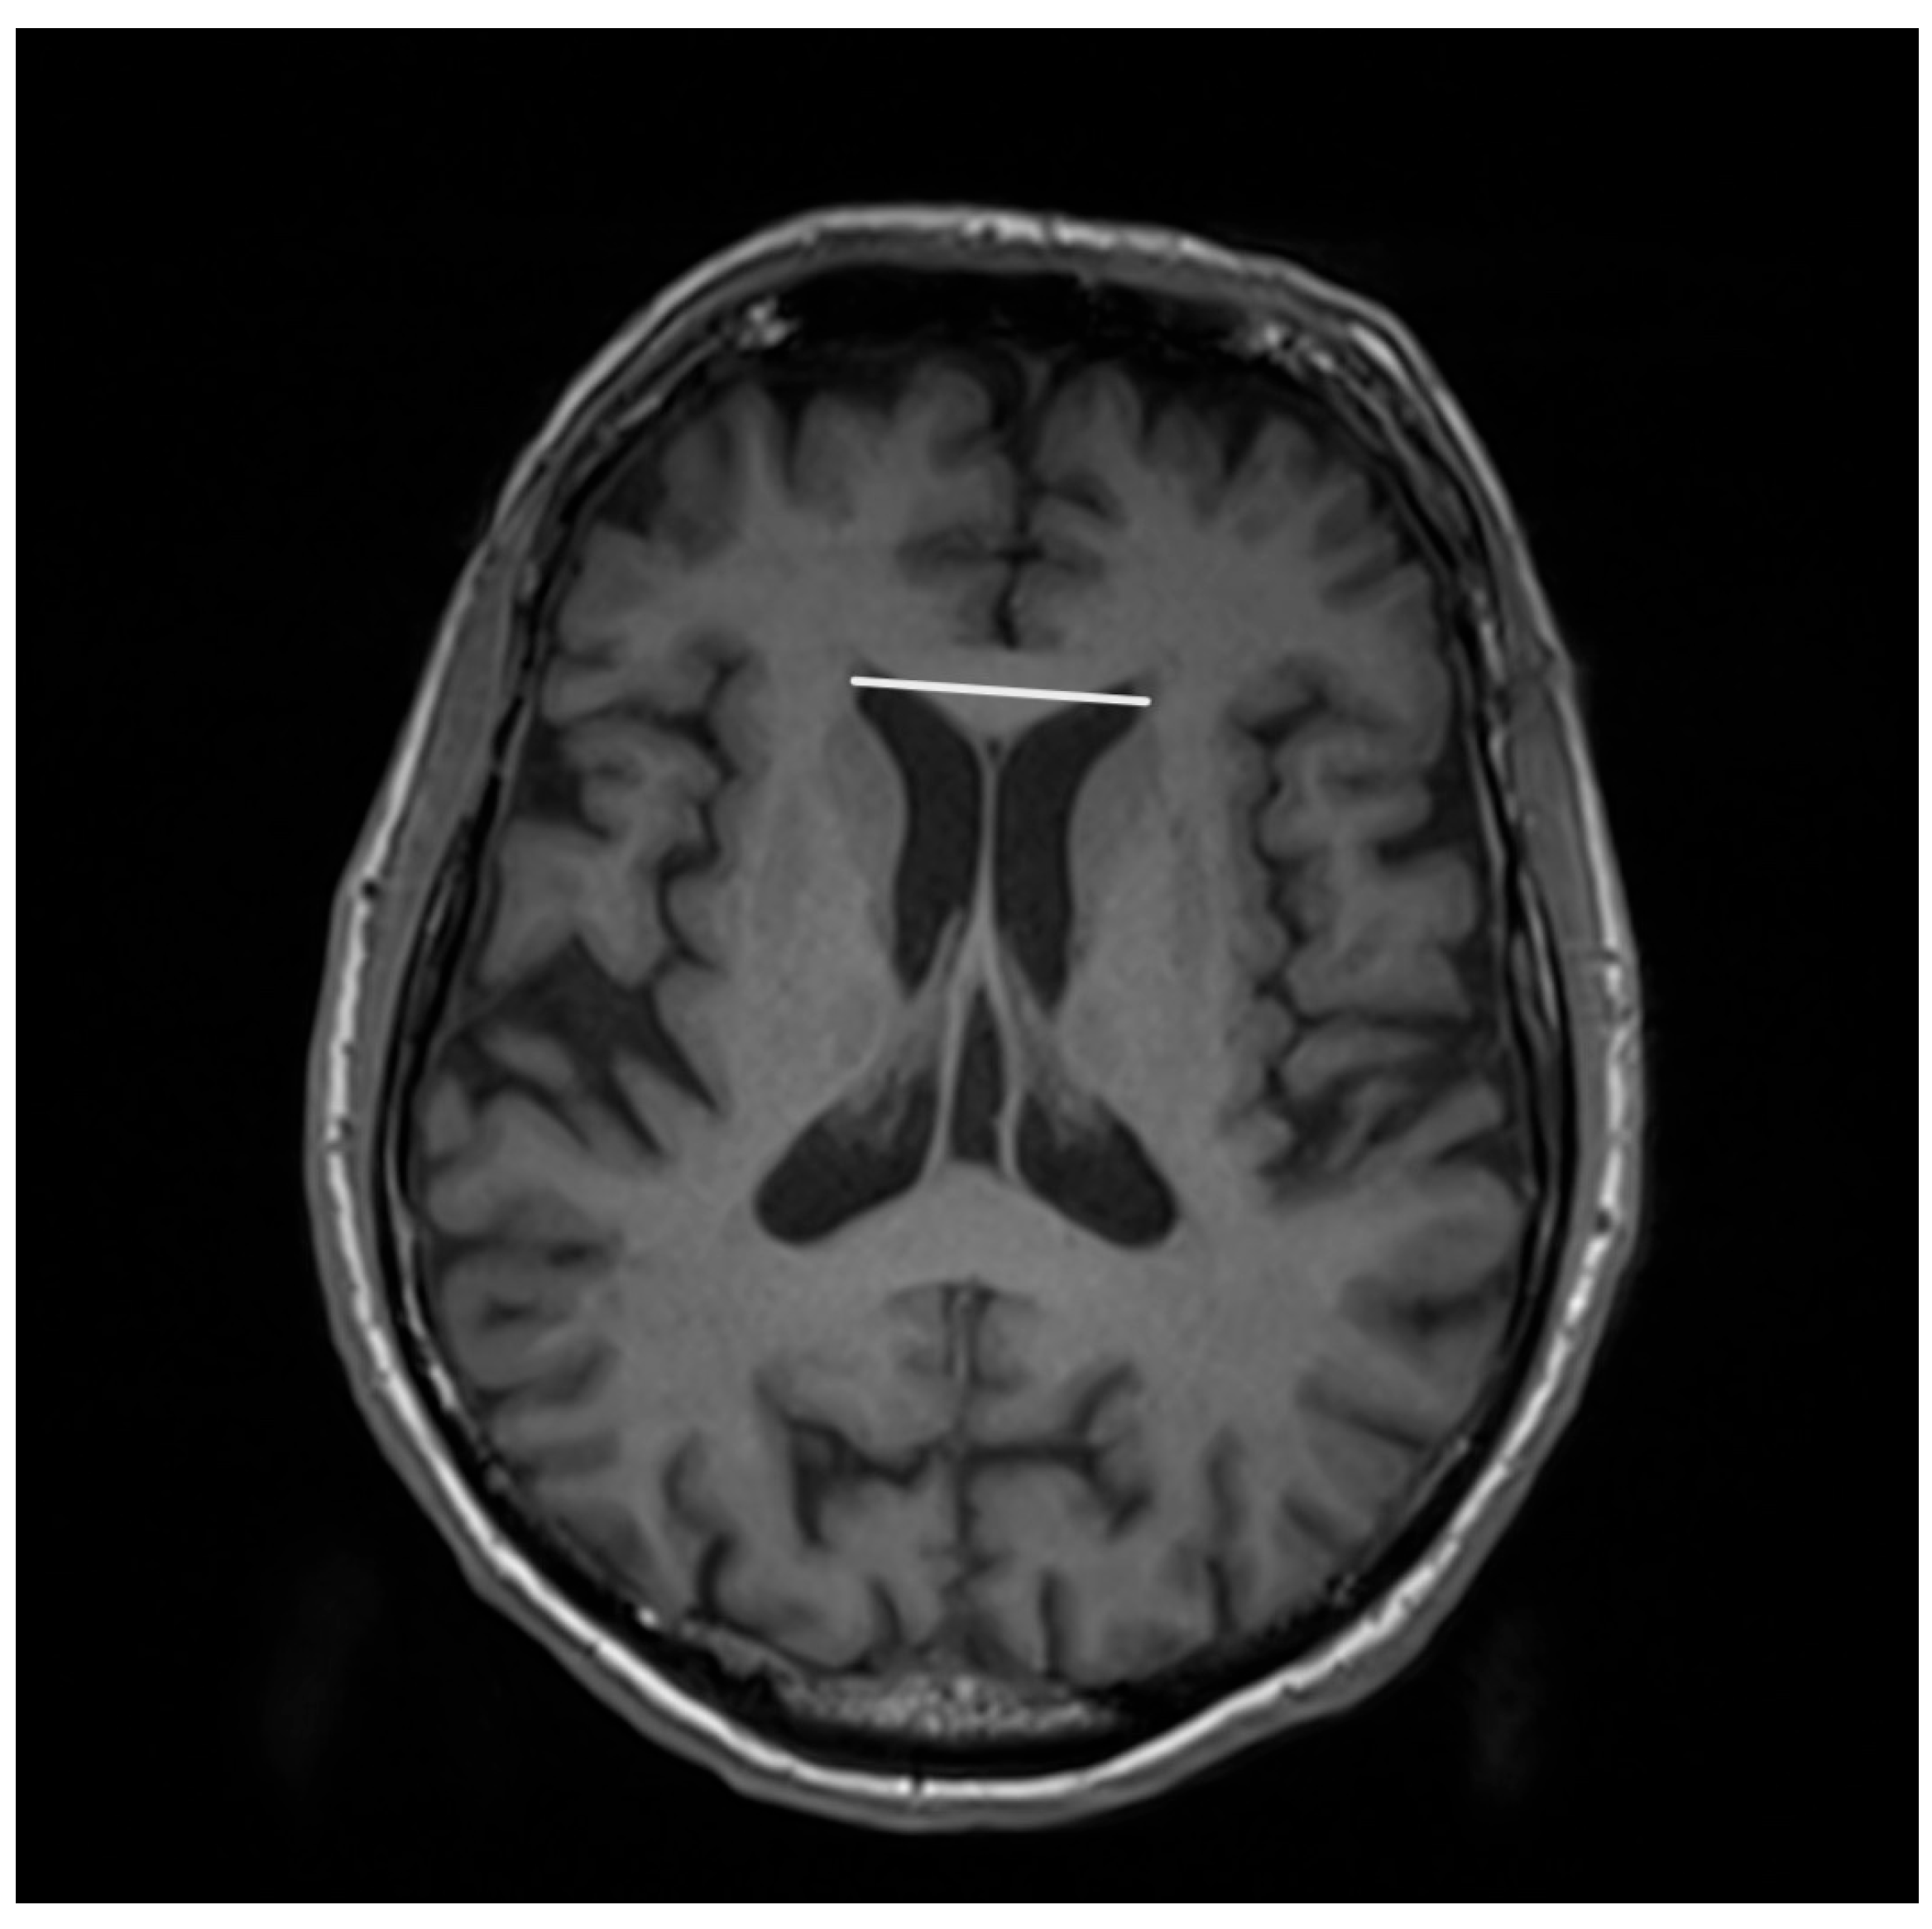

- Lenka, A.; Pasha, S.A.; Mangalore, S.; George, L.; Jhunjhunwala, K.R.; Bagepally, B.S.; Naduthota, R.M.; Saini, J.; Yadav, R.; Pal, P.K. Role of Corpus Callosum Volumetry in Differentiating the Subtypes of Progressive Supranuclear Palsy and Early Parkinson’s Disease. Mov. Disord. Clin. Pract. 2017, 4, 552–558. [Google Scholar] [CrossRef]

- Whitwell, J.L.; Tosakulwong, N.; Botha, H.; Ali, F.; Clark, H.M.; Duffy, J.R.; Utianski, R.L.; Stevens, C.A.; Weigand, S.D.; Schwarz, C.G.; et al. Brain volume and flortaucipir analysis of progressive supranuclear palsy clinical variants. Neuroimage Clin. 2020, 25, 102152. [Google Scholar] [CrossRef] [PubMed]

- Agosta, F.; Kostić, V.S.; Galantucci, S.; Mesaros, S.; Svetel, M.; Pagani, E.; Stefanova, E.; Filippi, M. The in vivo distribution of brain tissue loss in Richardson’s syndrome and PSP-parkinsonism: A VBM-DARTEL study. Eur. J. Neurosci. 2010, 32, 640–647. [Google Scholar] [CrossRef]